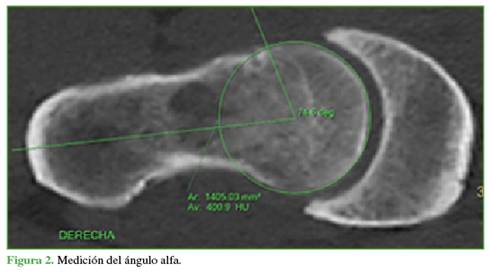

Trastorno morfológico: se analizaron las radiografías para definir el tipo de trastorno morfológico, clasificándolo en Pincer, Cam o Mixto. Para definir una sobrecobertura (Pincer) se midieron el ángulo de cobertura lateral (ángulo de Wiberg [ángulo centro-borde lateral]; normal entre 25 y 40°) y el índice acetabular (normal 0-10°), además del signo de entrecruzamiento de paredes acetabulares. En cuanto al trastorno femoral, se midió el ángulo alfa en la proyección de Dunn a 45°, tomando como valor normal <55° (Wawrick) (Figura 2). Las mediciones estuvieron a cargo de especialistas en estudios por imágenes que no formaron parte de la investigación.

Se analizó el tipo de trastorno morfológico, el 85,71% tenía un trastorno mixto (24 casos); el 3,57%, uno de tipo Cam (1 caso) y el 10,71%, uno de tipo Pincer (3 casos). Respecto al trastorno femoral, se midió el ángulo alfa en las radiografías (proyección de Dunn a 45°) o en el corte oblicuo axial en la TC o RM. El ángulo alfa promedio midió 60,6° (rango 45-76); el ángulo de Wiberg promedio, 33,6° (rango 24-46) y el ángulo de inclinación acetabular (ángulo de Tönnis) promedio, 3,5° (rango 0-10).